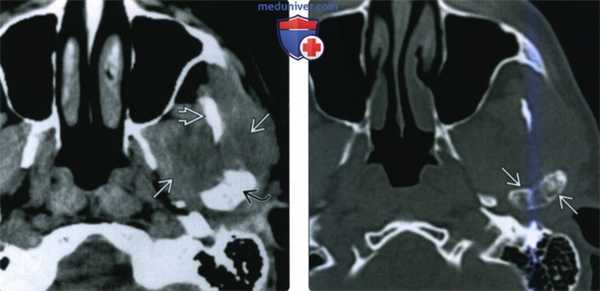

(Слева) На аксиальной КТ с КУ в мягкотканном окне визуализируется гиподенсная опухоль (хондросаркома без включений кальция), окружающая ветвь нижней челюсти и распространяющаяся вокруг венечного отростка и мыщелка.

(Справа) На аксиальной КТ в костном окне определяется вздутие мыщелка и шейки нижней челюаи с наличием хондроидных кальцинатов. Отсутствие типичных для хондросаркомы кальцинатов в мягкотканном компоненте затрудняет диагностику.

(Слева) КТ с КУ, мягкотканное окно. Другой пример хондросаркомы жевательного пространства, на этот раз без кальцификатов. Образование низкой плотности окружает ветвь нижней челюаи и распространяется вокруг венечного отростка и мыщелка.

(Справа) КТ в костном окне, аксиальная проекция. Мыщелок и шейка нижней челюсти деформированы и содержат кальцификаты. Отсутствие характерных кальцификатов в мягкотканной части опухоли делает постановку диагноза затруднительной.